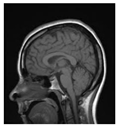

| Original Image | Marked Image | Encrypted Image (Chaotic) | Decrypted Image | Correlation between Extracted Blocks and Original Blocks |

![]() | ![]() PSNR = 35.99 dB SSIM = 0.97 | ![]() PSNR = 12.17 dB SSIM = 0.1035 | ![]() PSNR = 35.99 dB SSIM = 0.97 | ![]() |